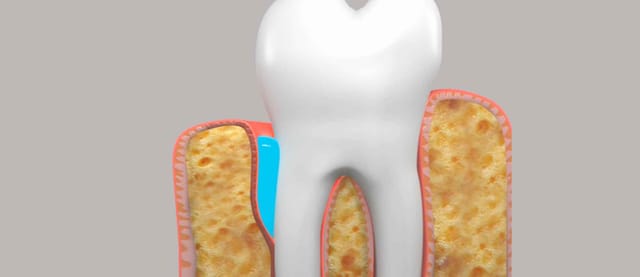

Advanced periodontal disease results in the loss of supporting bone that surrounds the teeth. Bone regeneration may be necessary using the patient's own bone or various bone substitutes.

When a tooth is extracted and an implant is to be placed (either simultaneously or in the future) it is always necessary to complete bone grafting within the residual sockets that are left behind after the roots of the tooth are removed.